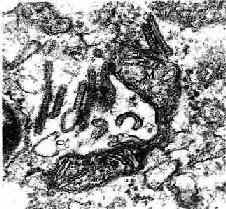

图10-6 郎格汉斯细胞电镜像 ×7800

↑球拍形Birbeck颗粒 M线粒体

(白求恩医科大学尹昕、朱秀雄教授供图)